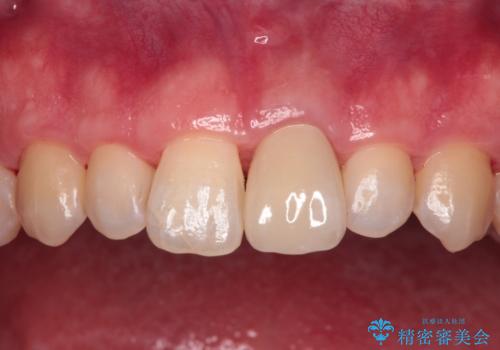

変色した前歯をオールセラミッククラウンに

- 転んだ際に欠けてしまった前歯の変色が気になるとのことで来院された患者様です。

診察やレントゲン写真より神経組織の失活が認められたため、根管治療、ファイバーコアによる土台築製後、オールセラミッククラウンにて補綴することとしました。

神経を取り除いた歯は時間とともに変色してきます。

クリーニングやホワイトニングでは改善できないため、オールセラミッククラウンなどによる補綴治療が必要となります。